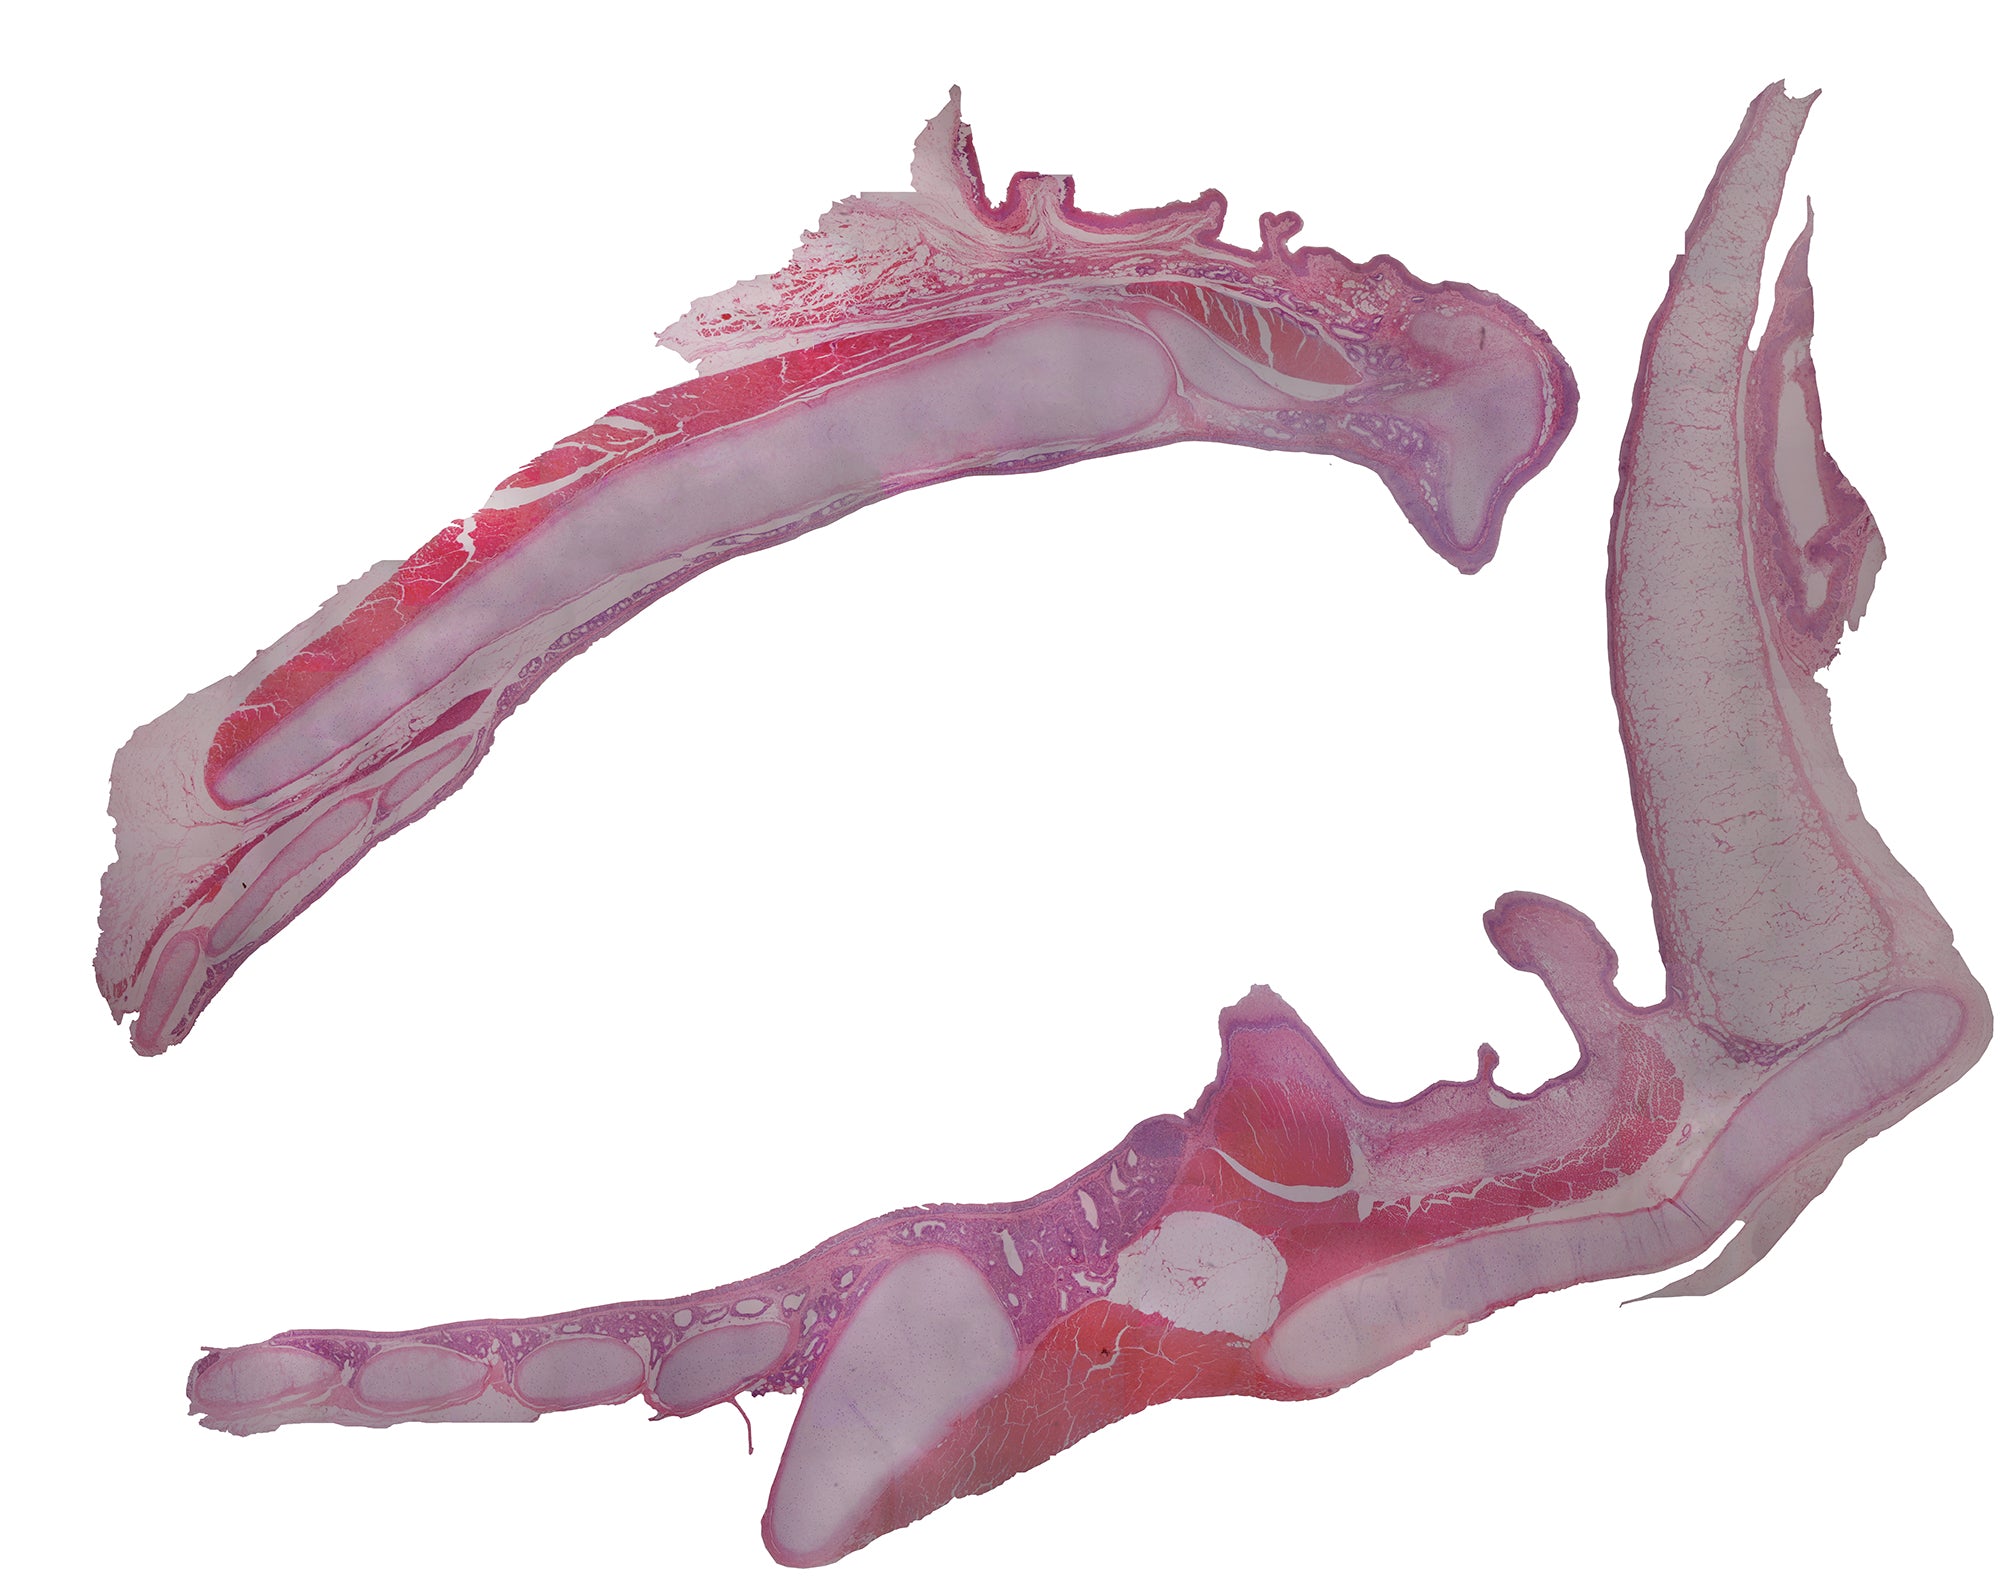

This slide is an H&E stained cross section of a larynx from a cat.